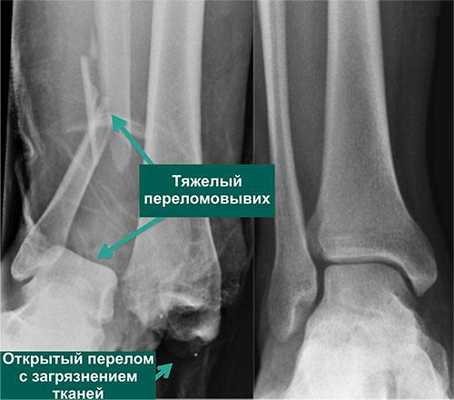

По статистике, 54% переломов и переломо-вывихов голеностопного сустава случаются в молодом возрасте, когда человеку важно сохранять трудоспособность. Эти травмы относятся к тяжелым повреждениям опорно-двигательного аппарата. Даже при качественном лечении они приводят к инвалидности в 3-12% случаев. Поэтому восстановление функций голеностопного сустава требует тщательного подхода, индивидуального для каждого пациента.

- Открытая репозиция с фиксацией погружными конструкциями. Таким путем лечат все открытые и часть закрытых переломов. В некоторых случаях после операции сустав дополнительно фиксируют гипсом.

Открытая репозиция с внутренней фиксацией

Метод применяют для лечения сложных переломов, когда невозможна ручная репозиция отломков и удержание их в нужной позиции с помощью гипса. Чтобы сопоставить костные фрагменты и надежно зафиксировать их, используют погружные элементы и конструкции: